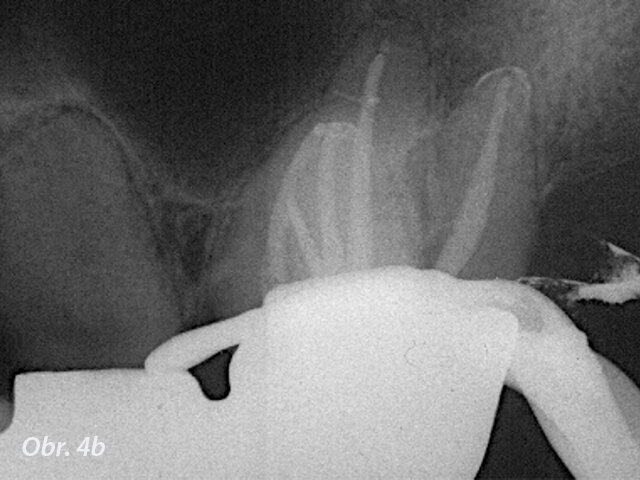

Hluboké rozvětvení kanálku. Vyplnění prvního kanálku kontrolované pod mikroskopem těsně pod místo lomu (šipka).

Vysoké zvětšení může pomoci při lokalizaci a opracování neprůchodných a kalcifikovaných kanálků, při hledání rozdvojených kanálků (obr. 3), odstraňování překážek z kanálku, jako výrůstků a kalcifikací, a při obturaci (obr. 4). Další základní endodontické procedury těžící z použití mikroskopu zahrnují ošetření vitální dřeně a regenerativní endodoncii, protože je možná pečlivá a šetrná manipulace s dřeňovými tkáněmi nebo krevními sraženinami. Lepší vidění také pomáhá při ošetření anomálií zubů, jako je dens invaginatus nebo srostlice.